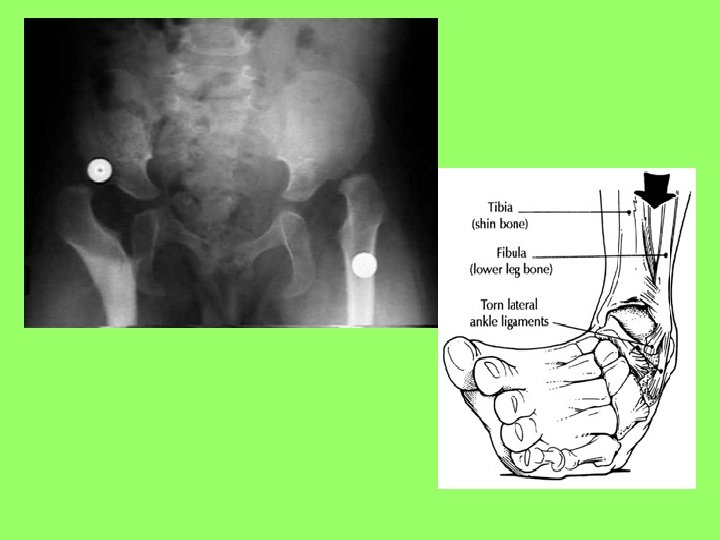

TALOCRURAL JOINT (ANKLE) • Highly modified hinge joint • Lateral and medial thickening of articular capsule prevents side-toside movement • Ligaments of the arch - hold bones in proper relationship - transfer weight

CLINICAL FOCUS • Sprain - bones of joint are forcibly pulled apart, surrounding ligaments are torn or pulled • Separation - bones remain apart after an injury • Dislocation - one end of bone is pulled out of the socket • Arthritis - inflammation of a joint (more than 100 types) osteoarthritis - wear and tear rheumatoid - caused by transient infection or autoimmune disease • Gout - increase in uric acid in the body accumulates as crystals in joints and tissues